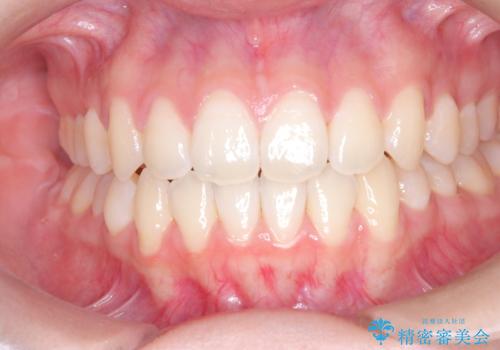

- 右上の小臼歯が大きくねじれており、噛み合わせや見た目に影響を与えている状態でした。診察の結果、インビザライン単独では十分な回転が得られにくいと判断。そのため、基本的な歯列の移動はインビザラインで行いながら、部分的にワイヤー矯正を併用するコンビネーション治療を計画しました。

まず、インビザラインで歯列全体を整えながら、スペースを確保しました。その後、部分ワイヤーを装着し、右上小臼歯の捻転を効率よく改善。ワイヤーの力を活用することで、より確実に歯の向きを整えることができました。治療後は、「しっかり噛めるようになり、見た目も自然になった」と患者様にもご満足いただきました。